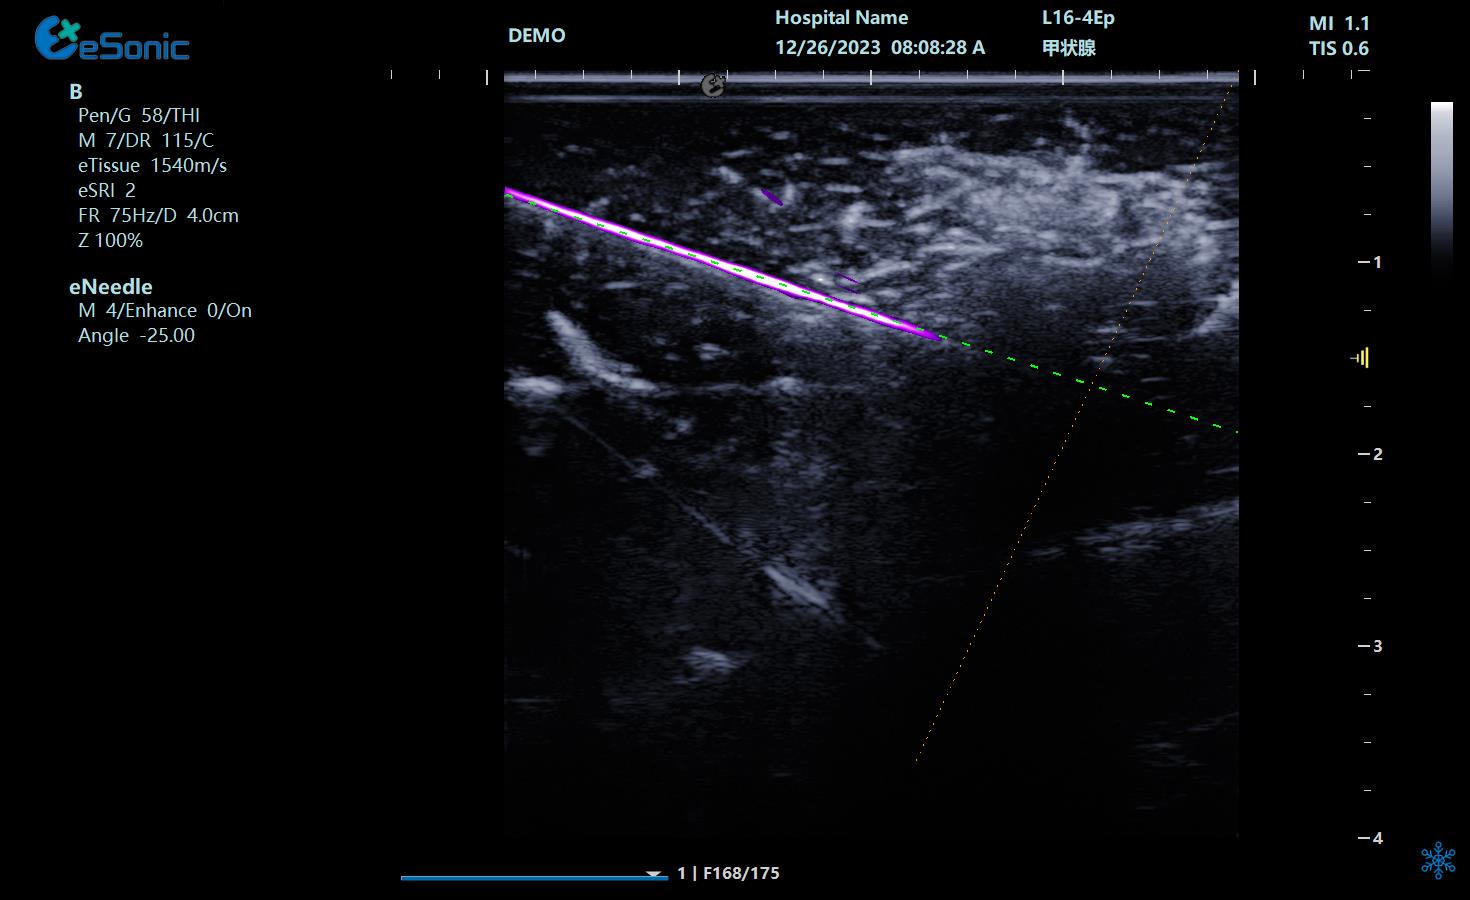

NeedleTS?穿刺针智能解决方案

?穿刺针增强显影?智能MAP?无磁导航

为临床医生有创穿刺保驾护航,真正实现精准导航。